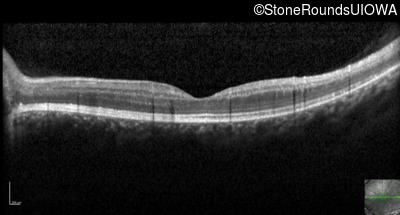

Optical Coherence Tomography - Right - 20/40 +2

Exemplar / OCT Stack

OCT Stack